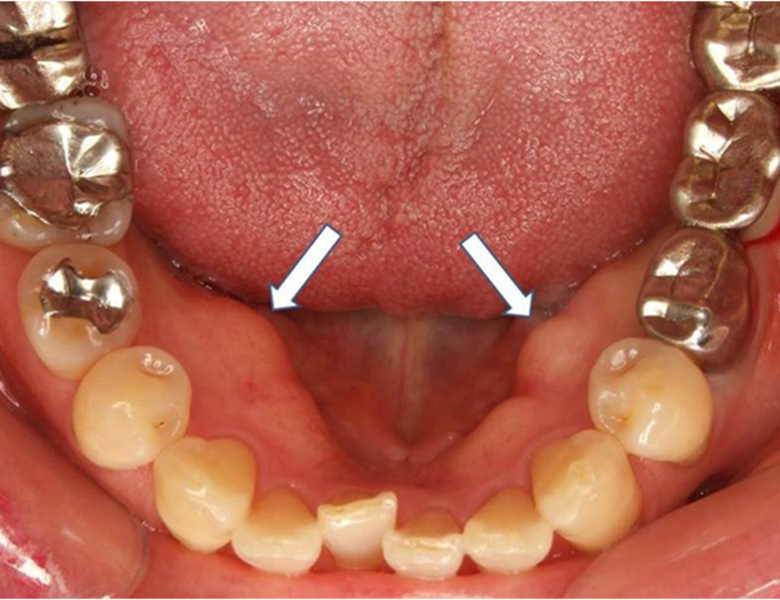

骨隆起(こつりゅうき)

上顎の真ん中や、下の歯の裏側の歯茎にできる、非常に硬い盛り上がりです。

腫瘍ではなく、骨が盛り上がったものです。

噛み締めや食いしばりの強い方によく見られます。

基本的には放っておいても大丈夫ですが、入れ歯が当たって痛む場合は処置を検討します。